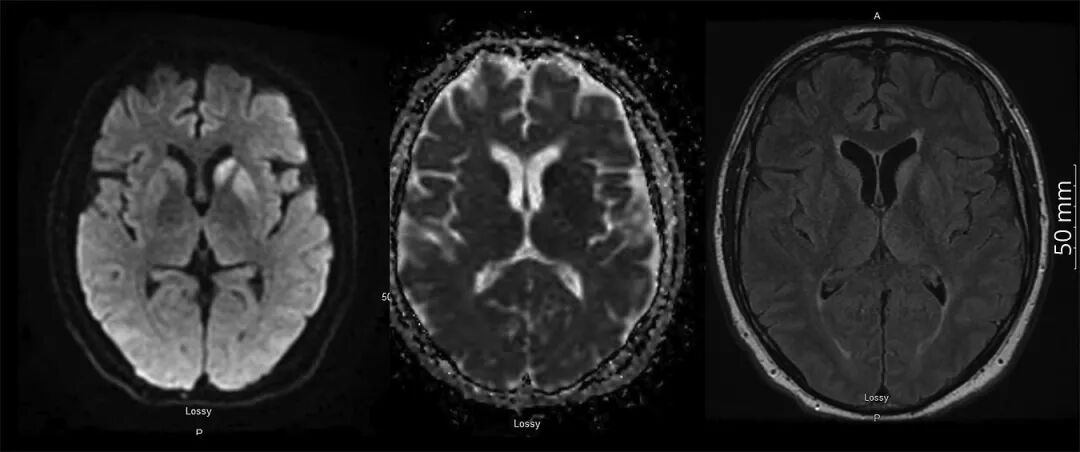

副肿瘤性脑脊液检测、单纯疱疹病毒PCR和隐球菌抗原检测均为阴性。常规EEG显示背景频率为7Hz,符合轻度至中度广泛性减慢,无局灶性、周期性或癫痫样特征。胸部、腹部和盆腔CT未发现恶性肿瘤。脑部增强MRI显示双侧尾状核和左前壳核扩散受限,造影时未见异常增强。T2 FLAIR序列显示轻度脑室周围白质高信号和轻度萎缩,脑室和脑沟扩大(图)。电诊断检查显示长度依赖性、严重的轴索性感觉运动性多发性神经病,累及上下肢。

图片图 DWI、ADC和T2 FLAIR序列显示左尾状核和前壳核弥散受限,相应区域ADC低信号和T2 FLAIR高信号

MRI结果结合患者快速进展的认知衰退和实验室检查无明显异常,强烈提示克雅氏病(CJD)。CJD的典型脑部MRI表现包括DWI或T2 FLAIR序列上尾状核、壳核或皮质区域(颞-顶-枕)高信号,通常局限于皮质回,称为皮质带状征。MRI上无增强使得炎症或自身免疫性脑炎的可能性降低。安排RT-QuIC脑脊液检测,其对CJD的特异性接近100%,敏感性为90%-95%。14-3-3为19,292 Au/mL(正常<1999 Au/mL),t-tau蛋白为2,935 pg/mL(正常<1,149 pg/mL)。RT-QuIC检测阳性。患者1个月后去世。脑部尸检最终确诊为散发性克雅氏病(sCJD),亚型MV1-2。患者未进行PNS病理检查